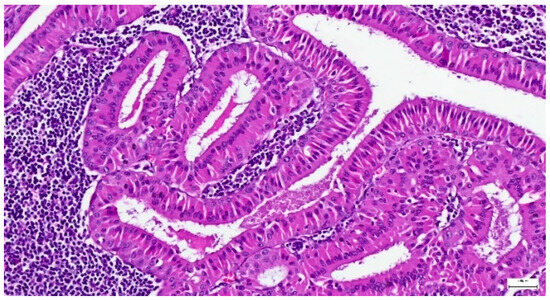

Only three cases of canalicular adenoma have been registered in our study, exhibiting well circumscribed single nodules, with a maximum diameter of 50 mm and complete capsular excision. The tumor epithelial cells were arranged in single or bilayered strands, anastomosing cords, canaliculi, or branching tubules, disposed in a loose connective stroma (Figure 17). The tumor showed CK7-positive immunoexpression, added to SMA-and p63-negative immunoexpression.

Figure 17. Tumor epithelial cells of a canalicular adenoma arranged in single and bilayered strands or anastomosing cords (H&E staining, 20×).